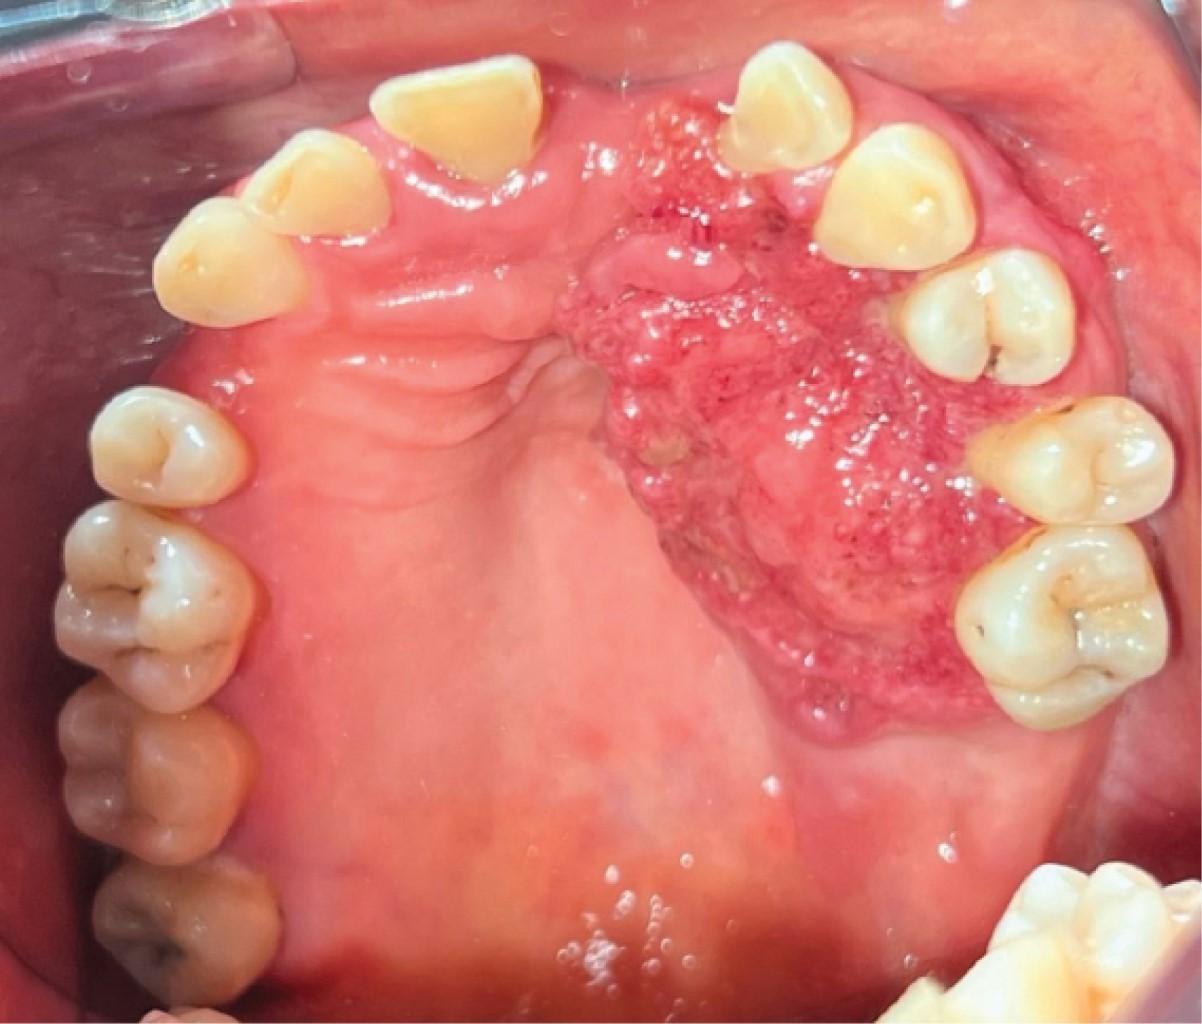

Figure 4